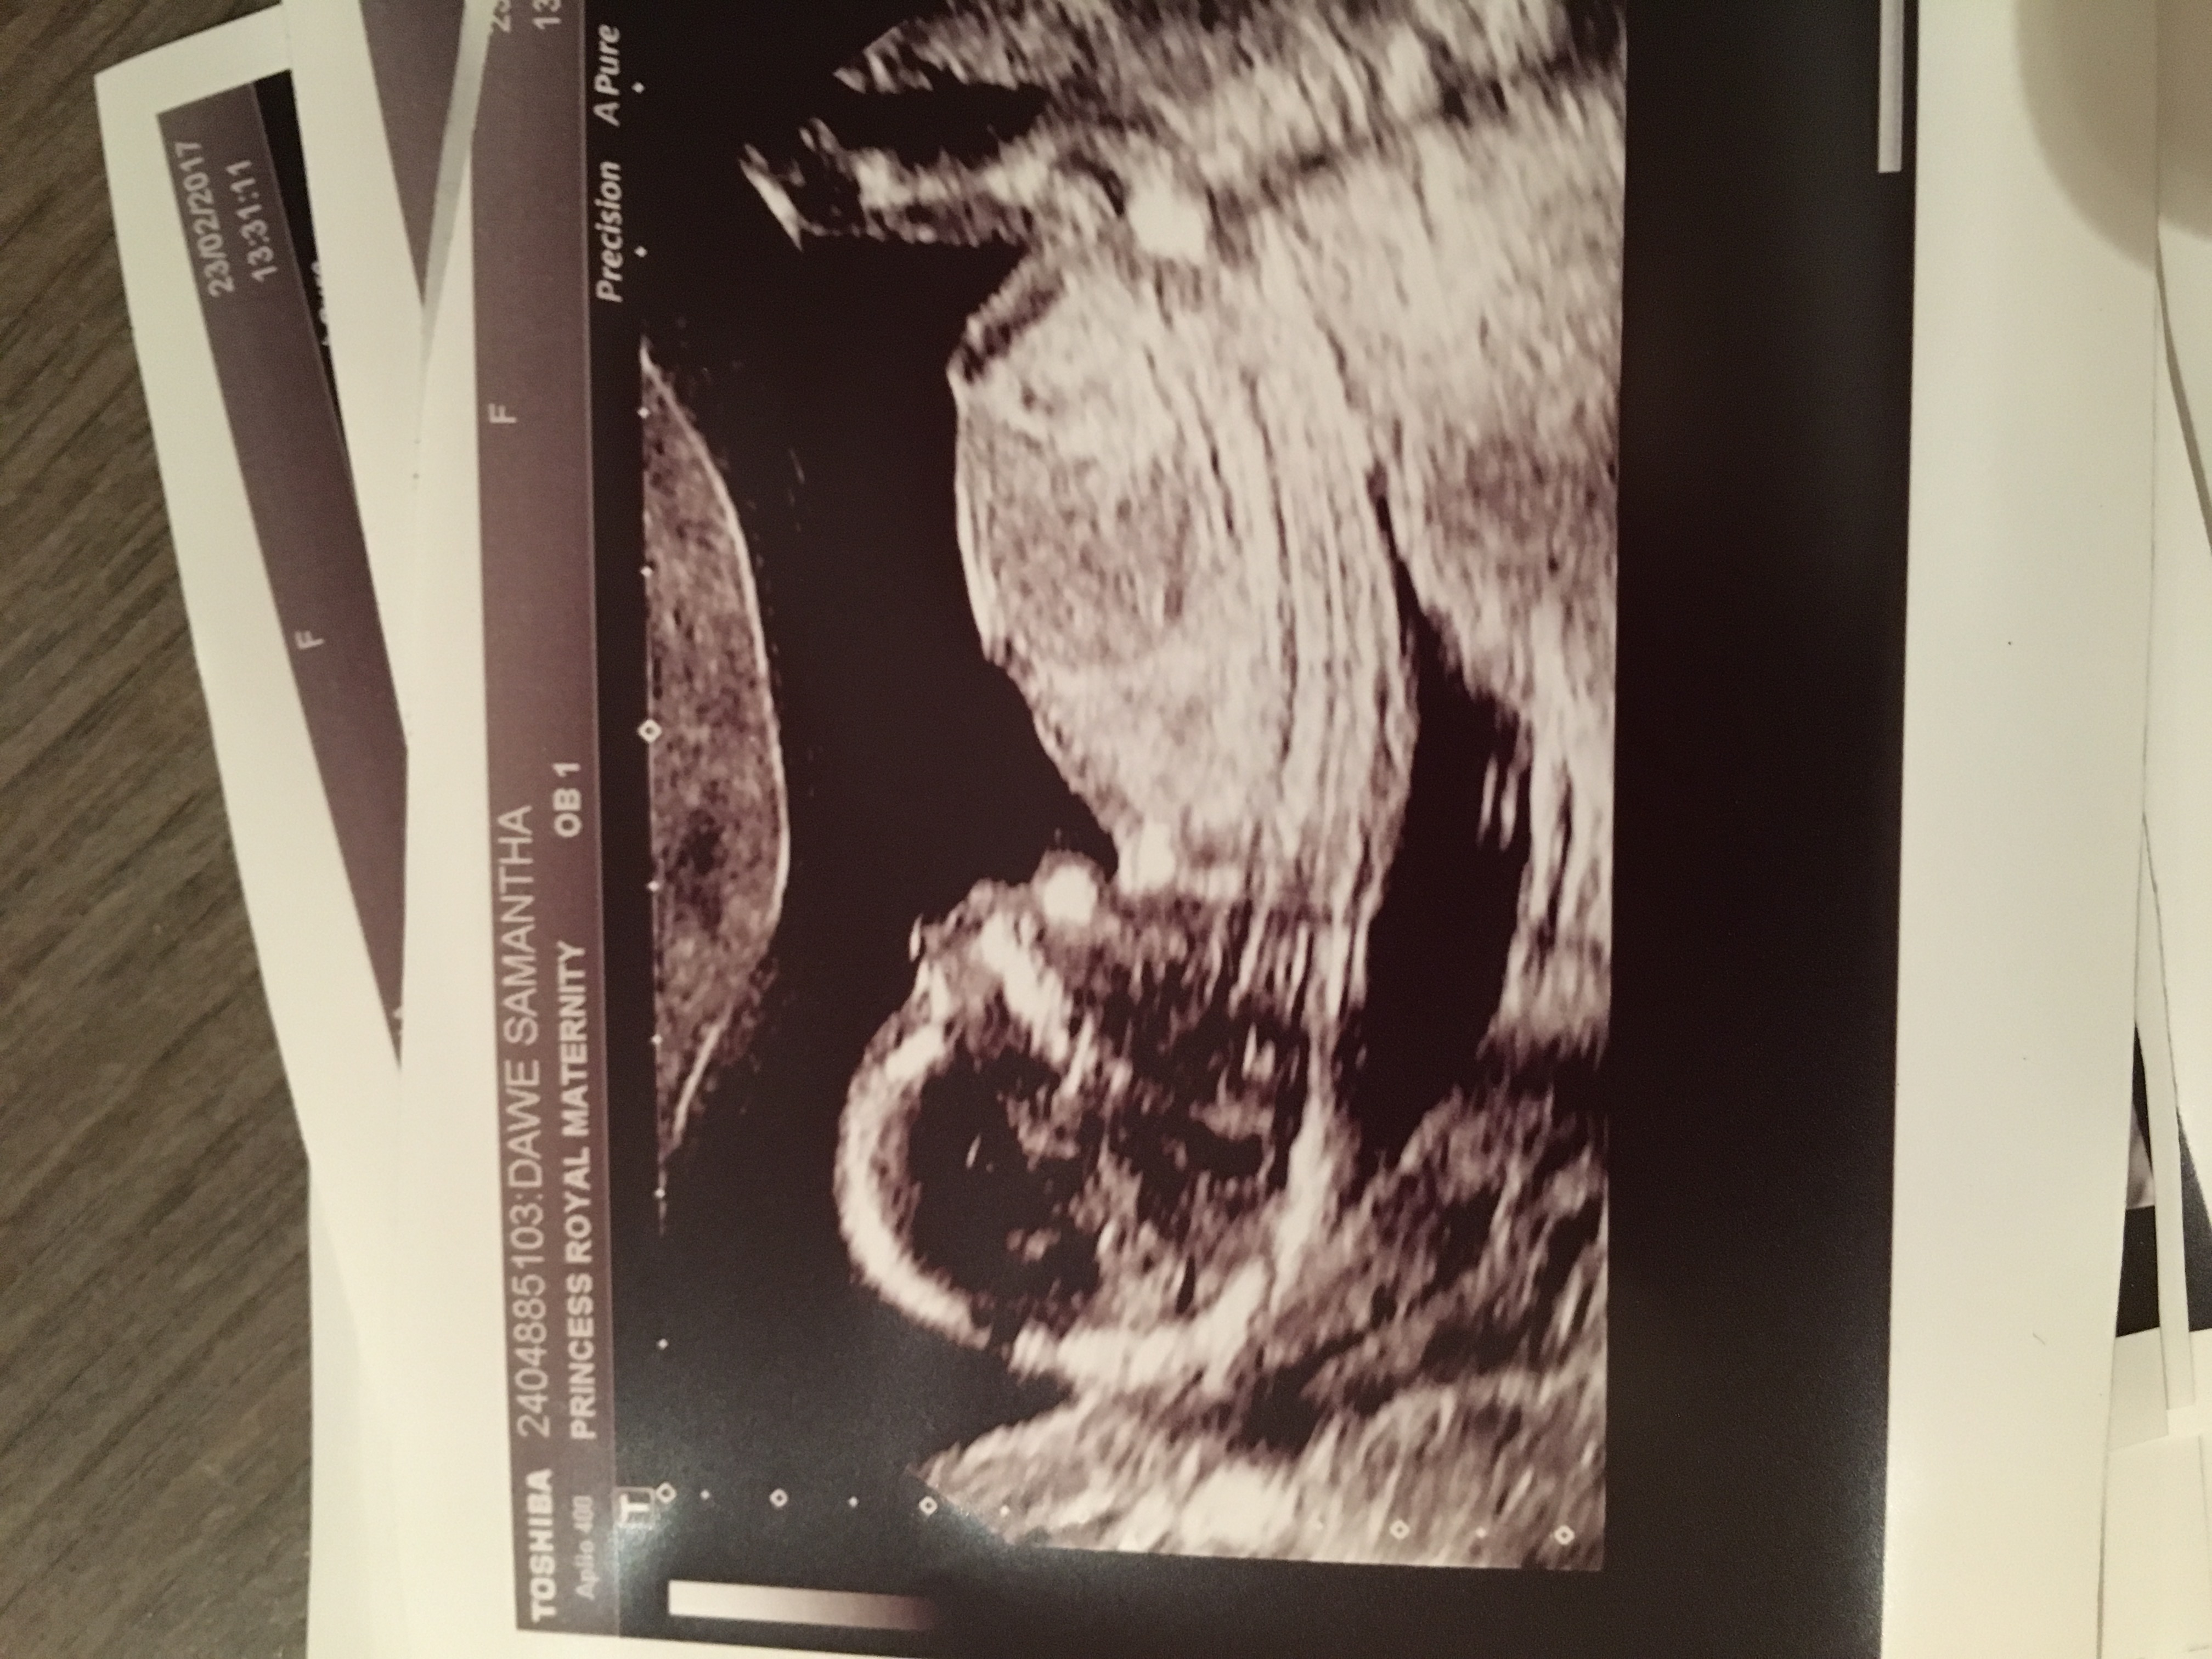

Attachment 35122

I am feeling boy, but not sure why. :)

Boy lean